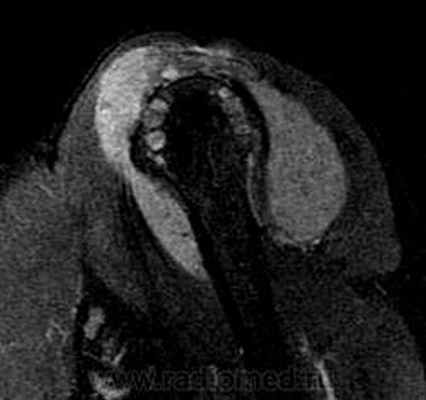

Пигментный виллёзонодулярный синовит - редкое заболевание с доброкачественным течением, характеризующееся пролиферативными изменениями синовиальной оболочки, отложением гемосидерина, образованием ворсинок, паннуса. Две разновидности: виллёзонодулярный бурсит и виллёзонодулярный тендосиновит. Частота - 2 на I 000 000. Преобладающий возраст • Виллёзонодулярный бурсит - 30-40 лет • Виллёзонодулярный тендосиновит -50-60 лет. Преобладающий пол - женский. Этиология. В 30% случаев развитию синовита предшествует травма сустава. Патоморфология. Пролиферация клеток синовиальных оболочек с образованием узлов, содержащих клеточный инфильтрат из фибробластов, лимфоцитов, макрофагов с жировыми включениями. Клиническая картина • Виллёзонодулярный бурсит -моноартрит. Чаще всего (80% случаев) поражается коленный сустав, реже - (с убывающей частотой) тазобедренный, голеностопный и плечевой суставы • Виллёзонодулярный тендосиновит - образование узелков в мышечных сухожилиях и связках сустава. Лабораторные исследования • Увеличение СОЭ • Синовиальная жидкость ксантохромная, с примесью крови • Биопсия синовиальной оболочки: узловая пролиферация, гемосидероз, инфильтрация мононуклеарными клетками. Рентгенологическое исследование • Остеопороз и наличие остеофитов нехарактерны • Артропневмография: множественные округлые дефекты наполнения синовиальной полости, обусловленные наличием узлов или гипертрофированных ворсинок синовиальной оболочки • МРТ - выявление гемосидерина и жировых включений. Артроскопия • Суставной хрящ приобретает коричневую окраску вследствие гемосидероза • Различной величины узлы коричневого цвета. Дифференциальный диагноз • Виллёзонодулярный бурсит • Липома - в аспиратах отсутствует ксантохромная жидкость • Остеоартроз - кисты возникают только на суставных поверхностях, подвергающихся нагрузке, тогда как при пигментном виллёзонодулярном синовите они образуются на всех суставных поверхностях. Остеофи-ты, напротив, более типичны для остеоартроза • Воспалительные арт-ропатии, дебютирующие моноартритом, - ревматоидный артрит, туберкулёзный артрит, анкилозирующий спондилоартрит и др. • Виллёзонодулярный тендосиновит - панглии (околосухожильные кисты): аспираты ганглиев содержат гелеподобную жидкость. Лечение хирургическое • Виллёзонодулярный бурсит • Тотальное иссечение синовиальной оболочки, вероятность рецидива заболевания составляет 25-40% • Лучевая терапия • Виллёзонодулярный тендосиновит - иссечение кист. Синоним. Синовит геморрагический МКБ. М12.2 Ворсинчато-узелковый (виллонодулярный) синовит (пигментный)

Рис. 5. А. Артроскопическая картина коленного сустава, при пигментно-ворсинчатом узелковом синовите (ПВУС). Б. После артротомии сустава.

В. Состояние хрящевого покрова. Хрящевой покров бедра и надколенника пропитан гемосидерином.